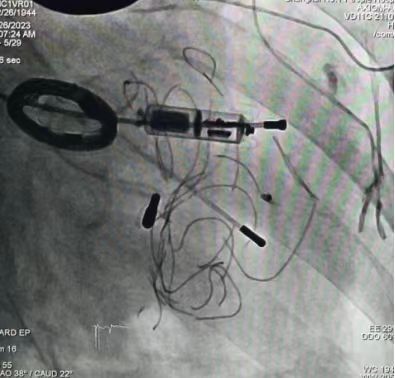

汪芳介绍,此次更换心脏起搏器最大的困难在于确定植入方式。“由于胡阿姨此前已经经历过34次手术,体内安装过22台起搏器。她的腹部和胸腔遍布疤痕,而且那些老式起搏器的线圈还留在体内无法取出,无法再更换传统起搏器。”汪芳说,考虑到这些因素,专家团队决定为胡根娣安装新一代的“Micra无导线起搏器”。

胡根娣体内残存的心脏起搏器线圈

此次安装的无导线起搏器重量不到2克,体积仅有1立方厘米,使用寿命可长达10年以上,兼容1.5T/3.0T核磁共振扫描,且植入过程简单,手术时间较短,可以大大减少并发症发生的风险。

日前,汪芳团队在市一医院松江院区为胡根娣施行了第35次手术,装上了第23台心脏起搏器。团队娴熟地通过下腔静脉途径,使用特殊的输送系统和导管跨过三尖瓣膜,将心脏起搏器植入到患者右心室间隔部,所有起搏参数均达到预期效果,术后起搏器工作正常。手术全过程耗时不到30分钟,患者全程保持清醒,无需气管插管和呼吸机辅助。